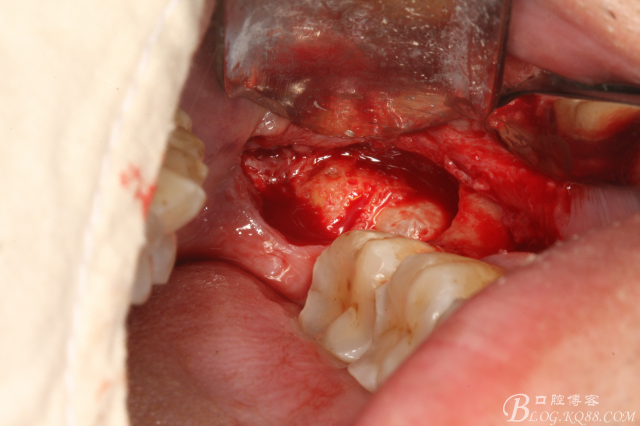

圖2.切開、翻瓣、去骨